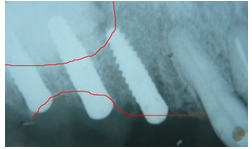

Foram realizados os procedimentos de sutura e radiografia periapical de controle do pós-operatório imediato (figura 10).